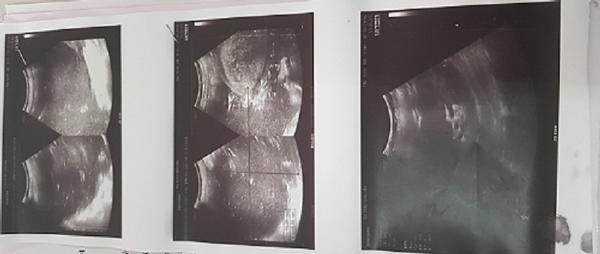

Sau khi thăm khám, hình ảnh siêu âm cho thấy dịch khu trú ổ bụng chưa loại trừ khối kích thước 198 x 130mm. Hình ảnh chụp cắt lớp cho thấy vùng hạ vị xuất hiện khối kích thước 17,5 x 23,6 x 24,1cm tỷ trọng dịch đặc trong có dịch khí với thành mỏng, khối choán chỗ trong tiểu khung và ổ bụng. Sau hội chẩn bệnh viện Ths.BSCK2. Đỗ Khắc Huỳnh chỉ định mổ lấy khối dịch.